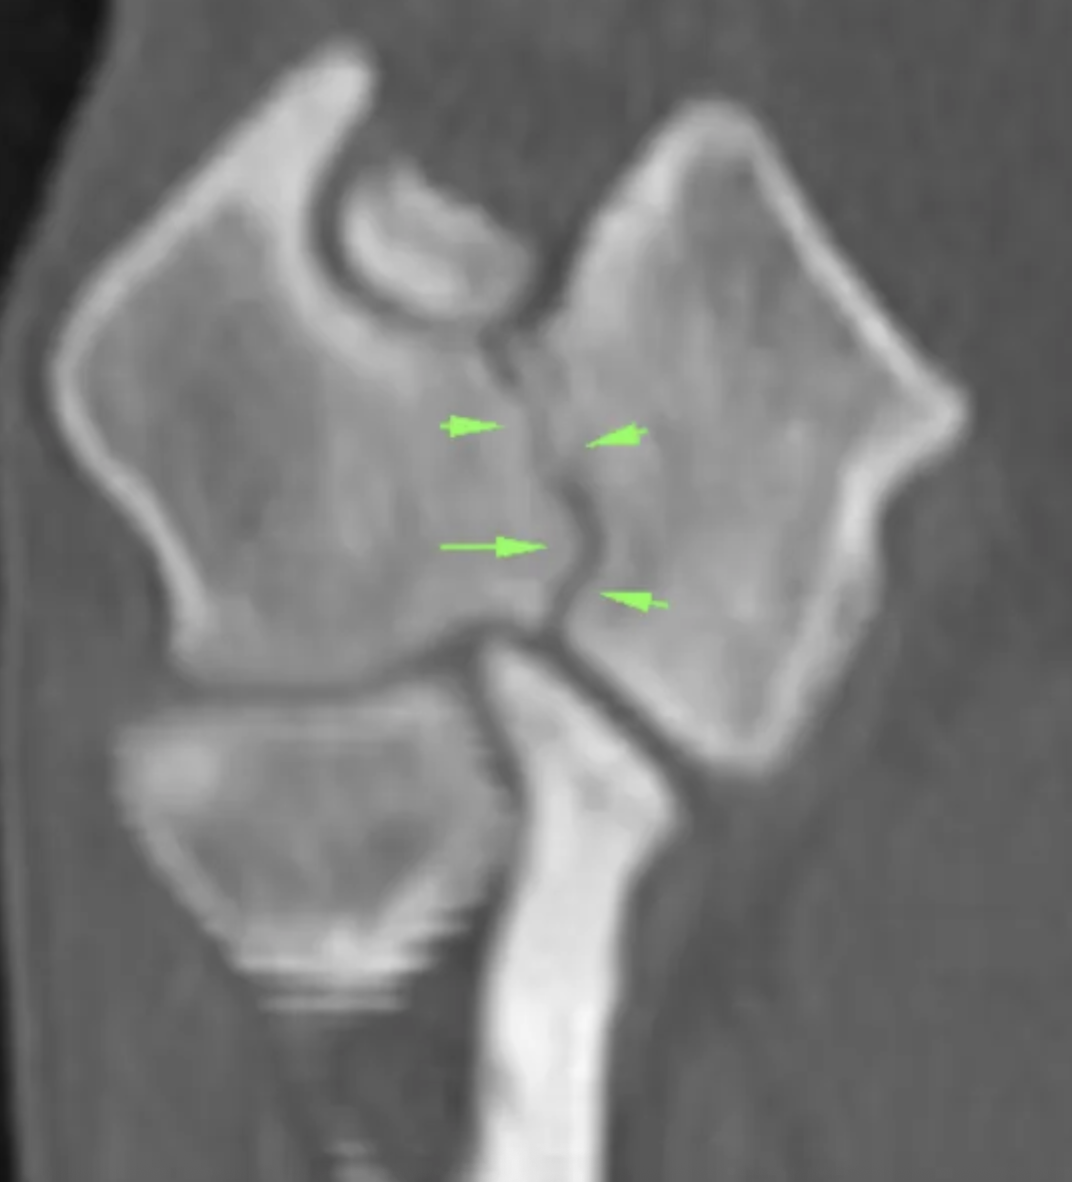

3. Scanner (CT-scan)

Examen de référence pour confirmer une ossification incomplète.

Il permet :

- de détecter précisément la fissure condylienne,

- d’évaluer sa largeur,

- d’analyser les deux coudes simultanément.

On observe une hypoatténuation à travers le condyle huméral, s'étendant de la surface articulaire au foramen supratrochléaire avec une zone de sclérose entourant cette lésion.